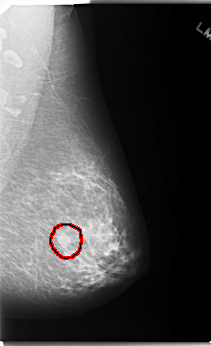

C_0124_1.LEFT_MLO

FILE: C_0124_1.LEFT_MLO.OVERLAY

TOTAL_ABNORMALITIES 1

ABNORMALITY 1

LESION_TYPE MASS SHAPE OVAL MARGINS MICROLOBULATED

ASSESSMENT 4

SUBTLETY 5

PATHOLOGY MALIGNANT

TOTAL_OUTLINES 1

BOUNDARY